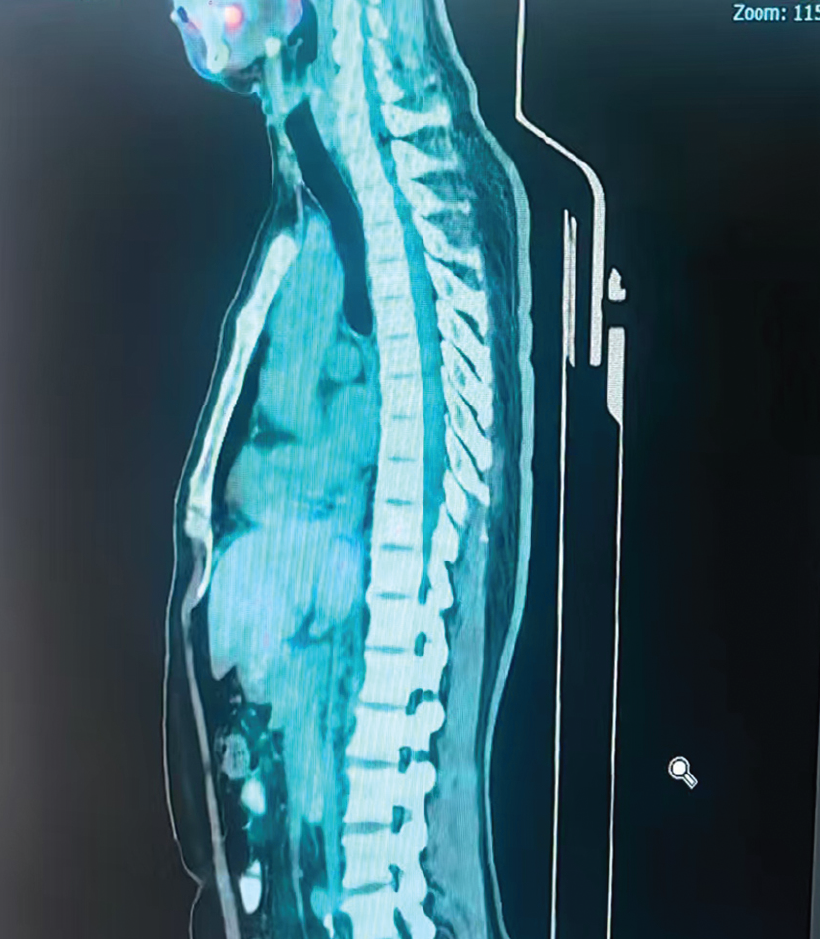

Before Treatment

After Treatment